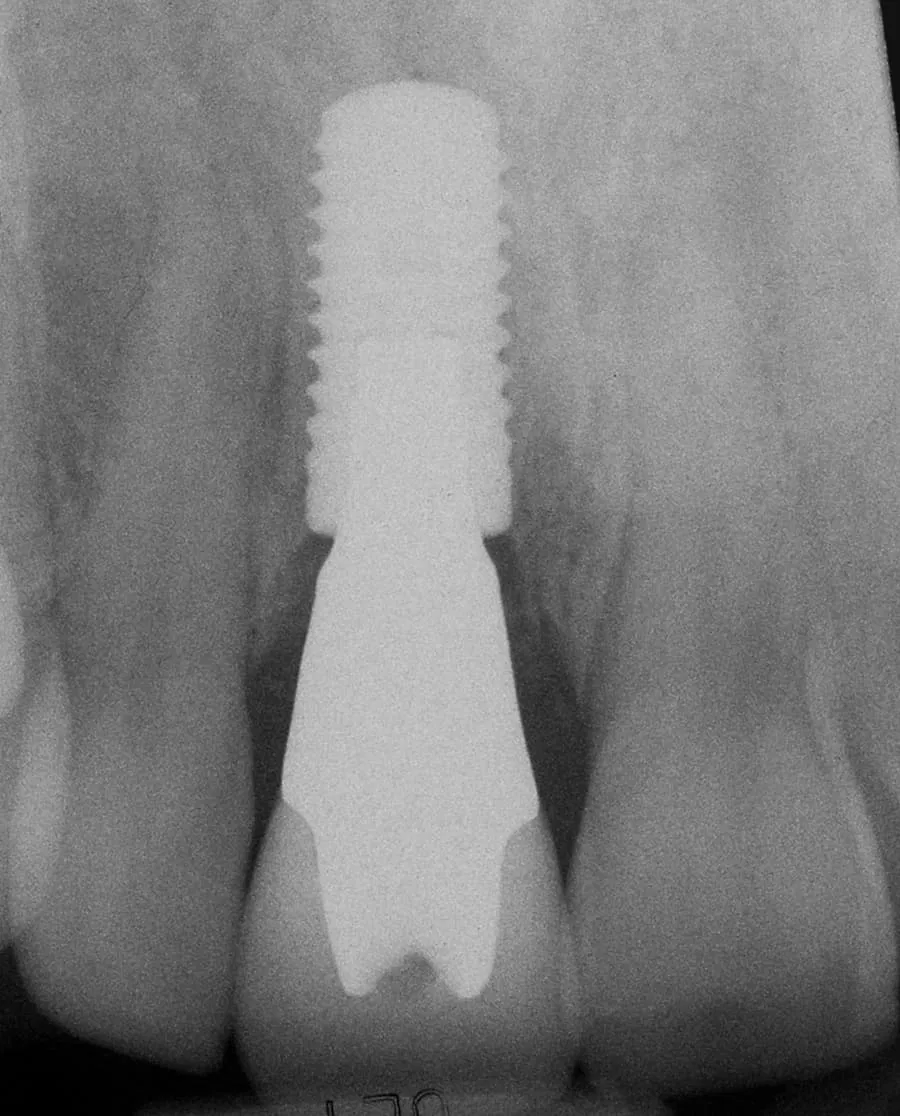

Immediate Implant Placement, Ceramic Implant Abutment, Ceramic Implant Crown

After: Single, all-ceramic crown attached to an all-ceramic, CAD-CAM designed and generated abutment (implant post). A delayed treatment approach was undertaken: tooth/root removal and grafting; 4 months healing; interim removable partial tooth replacement; implant placement; 6 months healing; proto-type (transitional fixed) implant crown, then the definitive implant restoration. The new tooth blends in perfectly with the natural, adjacent teeth.